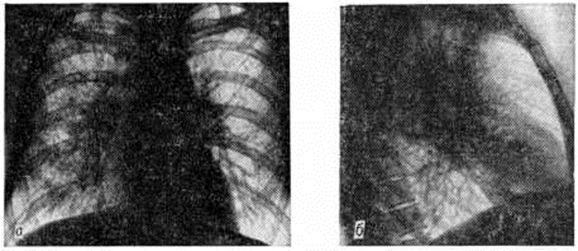

Поражение слизистых оболочек может быть изолированным, но чаще сочетается с саркоидами кожи. На миндалинах, мягком и твёрдом небе, языке обнаруживаются плотные опаловые узелки, окружённые гиперемическим ободком, или бледно-жёлтые бляшки, иногда гипертрофированные или изъязвлённые. Осложнения обычно связаны с прогрессированием лёгочного процесса — развитием бронхообтурационного синдрома, эмфиземы лёгких (смотри полный свод знаний), дыхательной недостаточности (смотри полный свод знаний), лёгочного сердца (смотри полный свод знаний), сердечной недостаточности (смотри полный свод знаний), реже с возникновением хронический почечной недостаточности (смотри полный свод знаний). Поражение глаз может привести к вторичной глаукоме (смотри полный свод знаний), катаракте (смотри полный свод знаний), снижению зрения вплоть до полной слепоты. Диагноз ставят на основании тщательного анализа анамнестических и клинико-рентгенол. данных, результатов поиска микобактерий туберкулёза, определения уровня кальциемии и кальциурии, отрицательных результатов реакции на туберкулин, а также других иммуно л. тестов, выявляющих угнетение клеточного иммунитета: реакции бластотрансформации лимфоцитов (смотри полный свод знаний) с фитогемагглютинином, спонтанного розеткообразования (смотри полный свод знаний: Розеткообразования тесты), торможения миграции лейкоцитов (эти реакции изучают также после подкожного введения туберкулина). Важное значение в диагностике Саркоидоз имеет гистологический или цитологический исследование поражённых тканей. Объектом для такого исследования может быть кожа, увеличенный лимфатических, узел, ткань лёгкого. Материал для биопсии (смотри полный свод знаний) получают при медиастиноскопии, бронхоскопии с трансбронхиальной пункцией узла, реже приходится прибегать к закрытой или открытой пункции лёгкого. Определённую помощь в диагностике Саркоидоз может оказать проба Квейма, которая, по некоторым данным, оказывается положительной в большинстве случаев Саркоидоз, по другим — у 50— 70% больных. Пробу выполняют путём внутрикожного введения 0,1 — 0,2 миллилитров специфического антигена, полученного из саркоидной ткани больного. Через 2—3 недель на месте инъекции появляется багрово-красный узелок, который ещё через 2—3 недель подвергают биопсии. Пробу считают положительной, если в биопсийном материале обнаруживают изменения, характерные для Саркоидоз Использование пробы ограничено из-за отсутствия стандартного антигена (отсюда, повидимому, и противоречия в оценке её диагностической ценности), а также отсроченности её результатов. Такие изменения, как моноцитоз, умеренная лейкопения, лимфопения, палочкоядерный сдвиг, ускорение РОЭ, имеют значение в оценке активности процесса. Для диагностики Саркоидоз глаза проводят многостороннее офтальмологический обследование больного с учётом признаков поражения других органов и систем. Диагноз Саркоидоз кожи ставят на основании исследования высыпаний, результатов диаскопии и гистологический исследования. Диагностика внутригрудного Саркоидоз в ряде случаев весьма затруднена и иногда требует пункционной биопсии лёгкого, чаще трансбронхиальной биопсии лёгкого (смотри полный свод знаний: Бронхоскопия, Бронхофиброскопия). В случае Саркоидоз бронхов бронхоскопия может иметь решающее значение для постановки диагноза. Рентгенодиагностика имеет особенно важное значение для распознавания внутригрудных форм Саркоидоз (нередко определяя первичный диагноз ещё до появления явных клинические, симптомов) и помогает при установлении диагноза в случае характерных поражений костной системы. При обследовании больных, помимо обзорной рентгенографии, используют томографию лёгких и средостения (смотри полный свод знаний: Томография)i; по показаниям применяют бронхографию (смотри полный свод знаний) и пневмомедиастинографию (смотри полный свод знаний). При I стадии Саркоидоз органов дыхания рентгенологически определяется расширение корней лёгких и средостения за счёт опухолевидного увеличения всех групп лимфатических, узлов грудной полости, преимущественно лимфатических узлов корней лёгких. Очертания корней лёгких и средостения имеют полициклический характер, тени передних и задних групп лимфатических, узлов средостения, накладываясь друг на друга, создают симптом «кулис», увеличение лимфатических, узлов средостения из-за суммации теней придаёт сердцу митральную конфигурацию (рисунок 6). На томограммах выявляется, что увеличенные лимфатических, узлы располагаются по окружности крупных бронхов в области их деления на долевые, сегментарные и субсегментарные ветви. Иногда лимфатических, узлы образуют дугообразные вдавления стенок бронхов, в ряде случаев ведут к нарушениям бронхиальной проходимости — образуются участки гиповентиляции, ателектаза. Для II стадии характерна картина очаговой диссеминации: определяется избыточный, петлистый рисунок в прикорневых и нижних отделах лёгких (стадия IIа), образование мелких (милиарных) очагов (стадия IIб), появление более крупных очагов диаметром 3 — 5 миллиметров (стадия IIв), формирование крупных очагов диаметром более 6 миллиметров (стадия IIг). Наиболее постоянным является сочетание интерстициальных изменений с очаговыми, занимающими преимущественно прикорневые отделы средних и нижних лёгочных полей (рисунок 7). III стадия характеризуется наличием распространённого фиброза, участков цирроза лёгких (рисунок 8). В некоторых случаях встречаются атипичные проявления Саркоидоз: одностороннее увеличение лимфатических, узлов, односторонняя диссеминация, наличие в лёгких одиночных или нескольких фокусов уплотнений, локализованное скопление очагов в пределах одного сегмента лёгкого. К атипичным относится также преимущественно верхушечная локализация очагов, более характерная для туберкулёза. Облегчить диагностику Саркоидоз может рентгенологическое обнаружение характерных изменений в скелете. В эпифизах фаланг кистей рук и в костях, образующих лучезапястные и коленные суставы, определяются одиночные или множественные округлые просветления диаметром 4 — 10 миллиметров со склеротическим ободком; реже костные изменения имеют разлитой характер. Дифференциальную диагностику до обнаружения характерных для Саркоидоз гранулем в биопсийном материале приходится проводить с многими заболеваниями, особенно системного характера. Внутригрудную форму Саркоидоз в I стадии процесса приходится дифференцировать с туберкулёзом внутригрудных лимфатических, узлов, медиастинальной формой лимфогранулематоза, во II — III стадиях — с диссеминированным туберкулёзом лёгких (смотри полный свод знаний: Туберкулёз органов дыхания), карциноматозом, хронический воспалительными лёгочными заболеваниями, пневмокониозами (смотри полный свод знаний), реже другими лёгочными диссеминированными поражениями. Рентгенологически при туберкулёзном бронхадените (смотри полный свод знаний) в отличие от Саркоидоз наблюдается преимущественно одностороннее увеличение лимфатических, узлов, они спаяны, очертания корня лёгкого бугристые. При лимфогранулематозе (смотри полный свод знаний) увеличение лимфатических, узлов достигает значительной степени, имеет асимметричный характер, часто преобладает увеличение лимфатических узлов средостения. Саркоидоз глаза дифференцируют с вялотекущими формами иридоциклита (смотри полный свод знаний) туберкулёзной или герпетической этиологии. Саркоидоз кожи дифференцируют с кольцевидной гранулемой (смотри полный свод знаний: Гранулема кольцевидная), лимфоцитомой кожи (смотри полный свод знаний), туберкулёзом кожи (смотри полный свод знаний: Туберкулёз внелёгочный), красными угрями (смотри полный свод знаний: Угри), гранулемой лица с эозинофилией (смотри полный свод знаний: Гранулема лица), красным плоским лишаем (смотри полный свод знаний: Лишай красный плоский), гемодермиями (смотри полный свод знаний). Лечение саркоидоза в случае развития осложнений комплексное, включает различные симптоматические средства и методы вплоть до оперативного лечения осложнений (при Саркоидоз глаза) в сочетании с патогенетической терапией глюкокортикоидами. По данным З. И. Костиной с соавторами (1981), на фоне лечения глюкокортикоидными гормонами (смотри полный свод знаний) прогрессирование заболевания и его рецидивы наблюдаются в 3 раза реже, чем без лечения. Поэтому глюкокортикоидная терапия считается целесообразной при всех формах и стадиях Саркоидоз, если на протяжении 3—5 месяцев динамического наблюдения не обнаруживается тенденции к спонтанной регрессии процесса. Если же заболевание отчётливо прогрессирует, лечение следует начинать незамедлительно. А. Е. Рабухин и соавторами (1975) рекомендуют следующую схему гормональной терапии: преднизолон в суточной дозе 30 миллиграмм в течение 1-го месяца, в дозе 25 миллиграмм на протяжении 2-го месяца, в дозе 20 миллиграмм в течение 3-го, а затем каждые 2— 3 недель дозу снижают на 2,5 миллиграмм. В поддерживающей дозе 7,5—5 миллиграмм терапию продолжают 6 месяцев и более. Можно применять другие глюкокортикоидные гормоны в эквивалентных дозах. При саркоидозе глаза преднизолон или дексаметазон назначают местно в виде подконъюнктивальных или ретробульбарных инъекций. Некоторые специалисты рекомендуют сочетать гормональную терапию с назначением противотуберкулёзных средств (смотри полный свод знаний), например, тубазида в дозе 10 миллиграмм, в тех случаях, когда у больного имеются остаточные изменения после перенесённого ранее туберкулёза (кальцинаты во внутригрудных лимфатических, узлах, плотные очаги в лёгких), а также при положительных туберкулиновых пробах. При наличии противопоказаний к назначению глюкокортикоидов можно использовать делагил (по 0,25 грамм 2 раза в день в течение 2—4 месяцев). На фоне лечения глюкокортикоидами или делагилом З. И. Костина (1977) рекомендует назначать витамин Е до 600 миллиграмм в день в течение 2— 6 месяцев Предпринимаются попытки лечить саркоидоз хлорбутином, азотиаприном, D-пеницилламином, а также левамизолом, однако результаты их применения ещё не получили всесторонней оценки. Лечение и диспансеризацию больных Саркоидоз проводят в специализированных противотуберкулёзных или пульмонологический учреждениях. Возникновение рецидива является показанием к проведению повторного курса лечения. Прогноз в большинстве случаев благоприятный; в ранних стадиях Саркоидоз возможно выздоровление, больные, как правило, сохраняют трудоспособность. Рецидивы заболевания в течение первых 2—5 лет после лечения возникают в 4% случаев. В связи с этим все больные подлежат диспансерному наблюдению по меньшей мере на протяжении 2 лет после клинического излечения. При внутригрудных формах Саркоидоз прогноз ухудшается по мере прогрессирования болезни. В III стадии терапия может привести лишь к временному улучшению или временной стабилизации процесса; трудоспособность больных в этой стадии утрачивается. Летальность при Саркоидоз — около 3—5%. Наиболее частые причины смерти — легочно-сердечная недостаточность и уремия. Профилактика сводится к предупреждению осложнений путём своевременного лечения Саркоидоз Меры первичной профилактики Саркоидоз не разработаны.